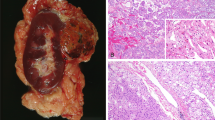

Main microscopic features and immunohistochemical studies are detailed in Table 1 and Supplementary Table 1 and illustrated in Fig. 1 and Supplementary Figs. 1 and 2. On gross examination, tumors were predominantly whitish or pale yellow and well-delimited (Fig. 1a). Eleven cases were pT1a, 5 pT1b, 2 pT2b, and two were pT3a due either to renal sinus fat infiltration (Fig. 1b) or perirenal fat invasion. No lymph node was detected on five radical nephrectomies. On microscopy, the dual component was either focal or diffuse, representing between 5 and 100% of the tumor surface (mean 20%). Generally, large squamoid-like cells were arranged in cohesive clusters of variable sizes localized in small spaces lined by small cells, giving them an alveolar or glomerular-like structure (Fig. 1c–h). The large cells had a vast eosinophilic cytoplasm and a big, sometimes angular nucleus with anisokaryosis. Emperipolesis was visible in all cases in various proportions, restricted to some clusters of large squamoid-like cells in some tumors (Fig. 1f–h). Rare mitotic figures were observed, restricted to the large cells. The nucleolar WHO/ISUP grade evaluated in large cells at 3 (in 17/18) or 2 (in 1/18), was higher than in small cells (grade 1 (in 2/18), 2 (in 14/18), or 3 (in 2/18)). Interestingly, a small component of grade 4 with sarcomatoid features was found in the tumor of patient #1, who subsequently developed metastasis. Neither sarcomatoid nor biphasic components were identified in his nodal mediastinal biopsy (Supplementary Fig. 2). Foamy macrophage clusters were found in 12 cases. Necrosis was observed in seven cases on 5–20% of the tumor surface, mostly at the center of the eosinophilic cell clusters. Upon routine IHC, the large eosinophilic cells of the biphasic component were always stained by the BCL1 (cyclin D1) antibody, unlike the conventional papillary component (Supplementary Fig. 1). FH expression was retained in all (8/8) tested cases (Supplementary Table 1).

a Gross picture of one of the two tumors (LPN) of patient #12 showing a well circumscribed white tumor with mastic and solid aspect. On hematoxylin, eosin saffron we illustrate: at low magnification ((b) ×2.5 magnification) pT3a tumor with sinus infiltration from patient #7 (yellow arrow surrounding large squamoid cells); at higher magnification the characteristic biphasic alveolo squamoid morphology showing: example of abrupt transition between areas with biphasic morphology and large cluster of squamoid-like cells (above the blue line) and classical papillary RCC type 1 (below the blue line) ((c) ×10 magnification) and different sizes of clusters of large eosinophilic cells nested arranged in alveolar-like spaces surrounded by small cells with either small clusters ((d) ×5 magnification; (f) ×2 magnification; (g) ×40 magnification), or larger clusters ((c) and (e) ×20 magnification; (h) ×40 magnification); (g–h) illustrate emperipolesis on large squamoid-like cells (green arrow in (f–h)).